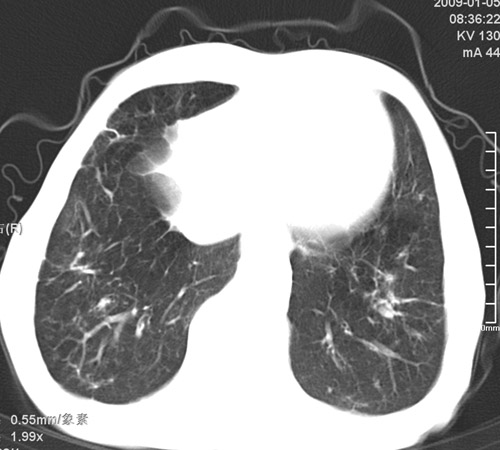

标题: CT17529:男 76 胸背部不适半月 胸透支气管炎 行CT检查 [打印本页]

标题: CT17529:男 76 胸背部不适半月 胸透支气管炎 行CT检查

意见 老年肺 少许炎症 肺大泡 右肺门略大 但支气管通畅  请各位高手指教如何下意见

间质纤维化伴少许炎症!另:肺大泡形成!

支持楼主意见,右肺门略大,可能为肺动脉增粗.

慢支肺气肿,肺动脉高压.